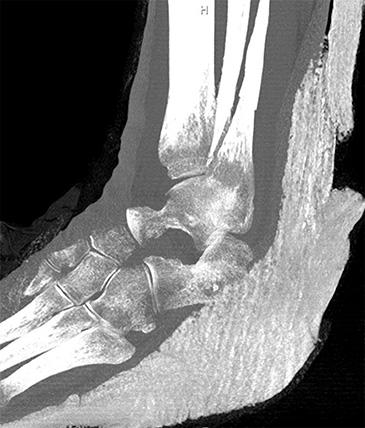

FRACTURA DE TOBILLO

El tobillo es la articulación que une la tibia y el peroné con los huesos del pie, permitiendo caminar y soportar el peso. Puede sufrir fracturas tras caídas o torceduras.

Algunas lesiones requieren sólo descanso e inmovilización, pero en otros casos es necesaria la cirugía para alinear y fijar los huesos.